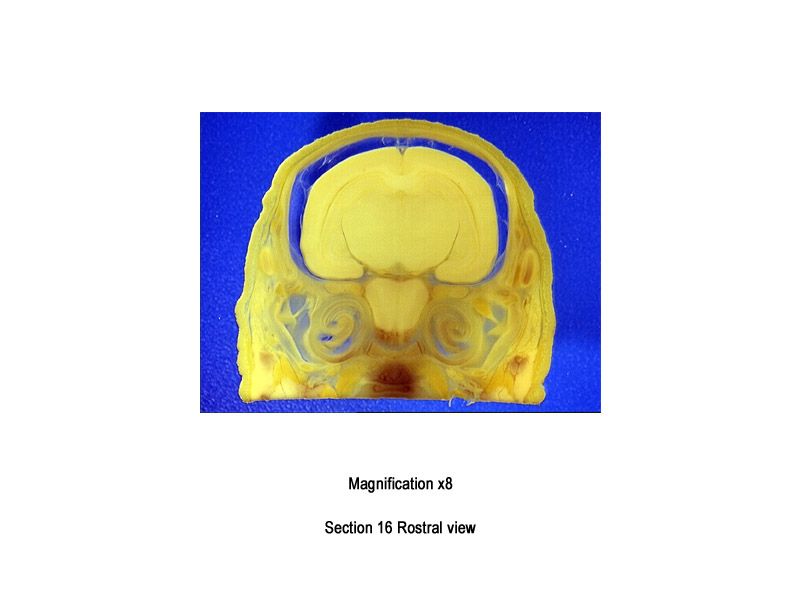

The images below show the normal appearance of Bouin's fluid fixed head sections in specimens at Day 29 of gestation (day mating observed = Day 0).

It is essential that both sides of each section is examined so that structures that exist is several sections can be visualised by the examiner in their mind as 3D.